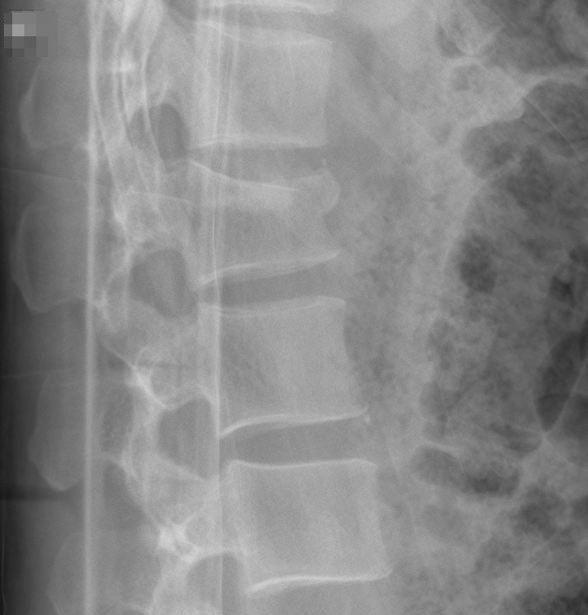

Lateral thoracolumbar Xray reveals multiple collapsed vertebrae What Is Thoracolumbar Spine X Ray  The lumbar spine is made up of five. Your thoracic spine is the middle section of your spine. The lumbar spine anteroposterior or posteroanterior view images the lumbar spine in its anatomical position. The vertebrae are separated by flat pads of. The lumbar spine generally consists of five vertebrae (see:. It starts at the base of your neck and ends. What Is Thoracolumbar Spine X Ray.